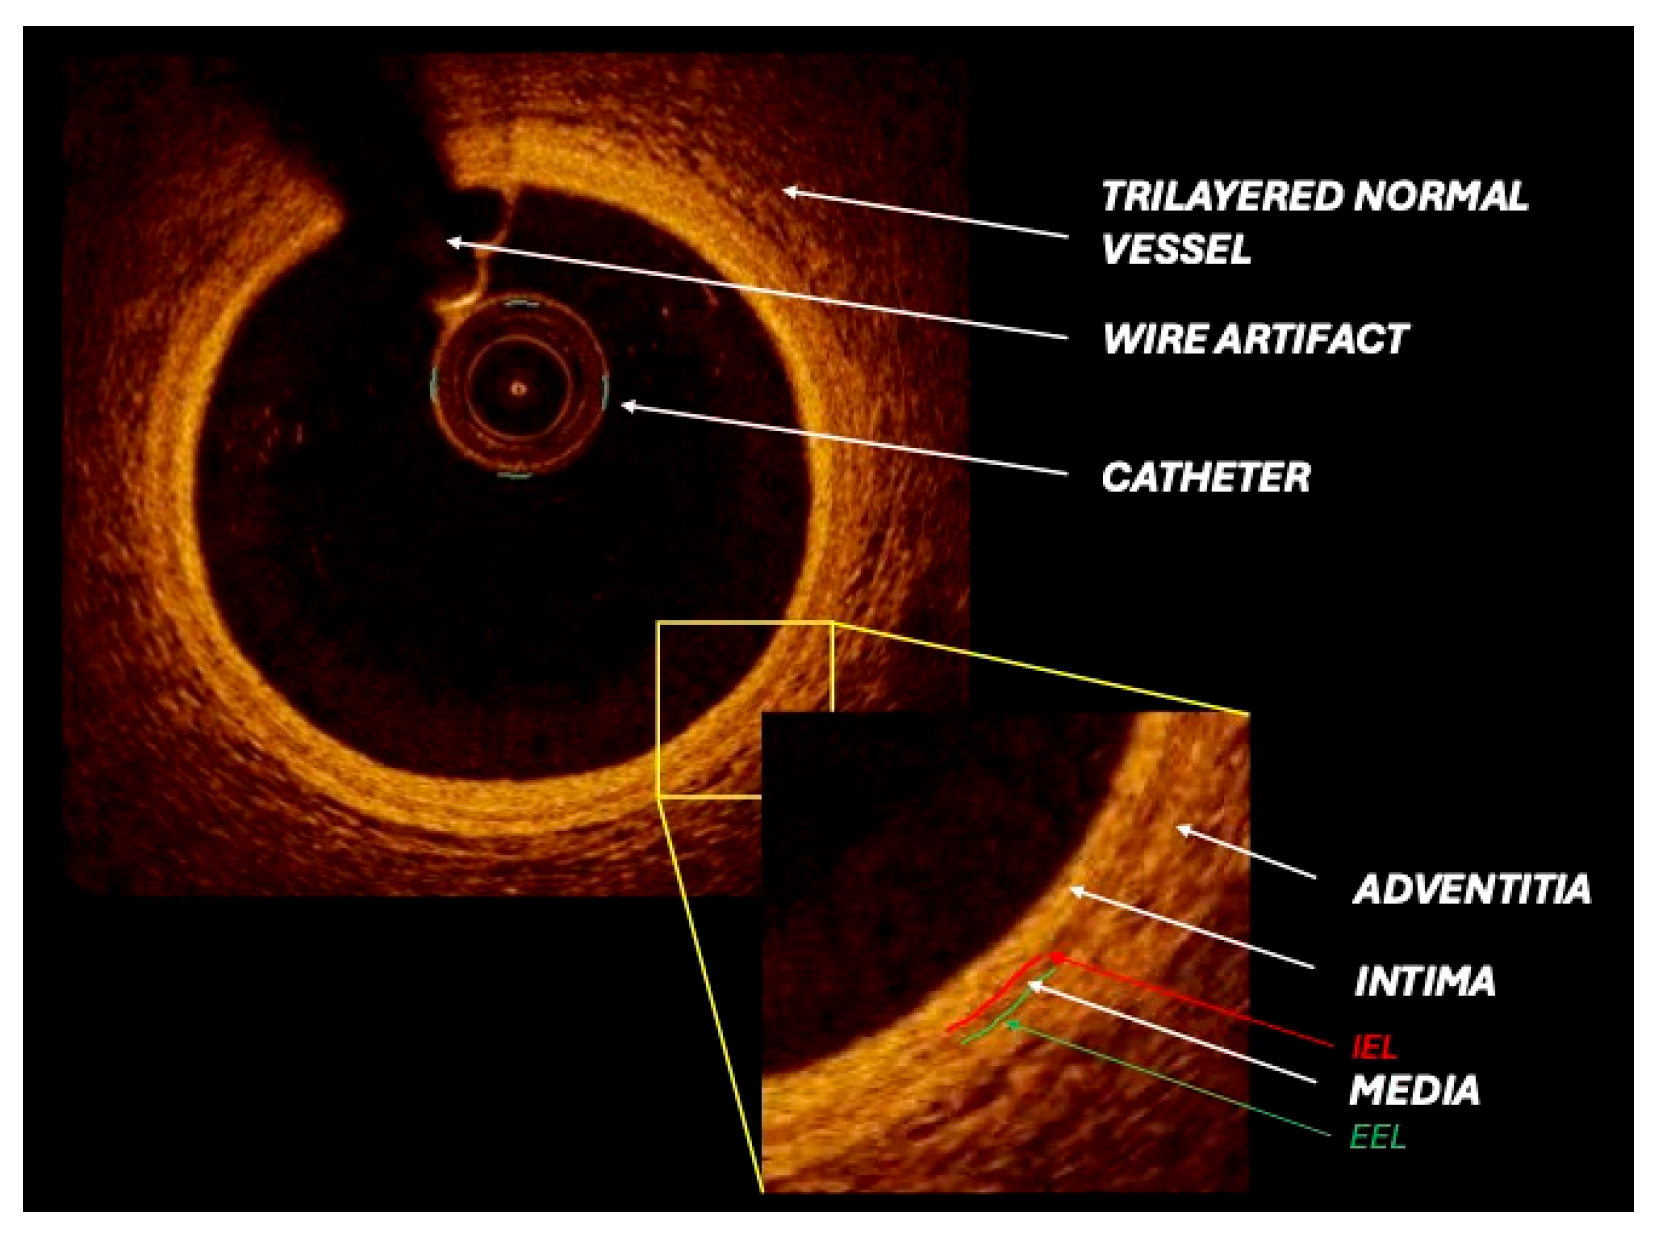

2.1. IVUS Technology